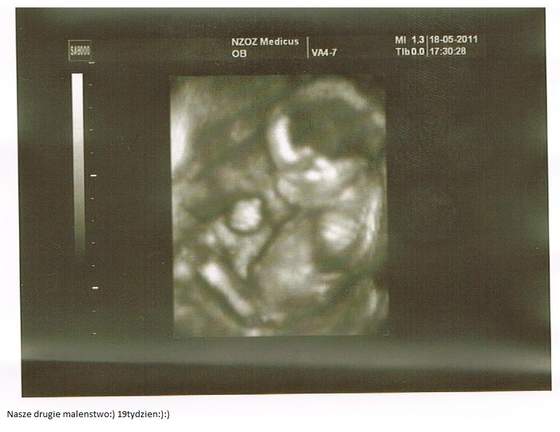

No to i ja sie na szybko pochwale:) W koncu jakos odetchnelam z ulga, bo z usg wyglada ze wszystko jest u maluszka w jak najwiekszym porzadku:-) Ciaze tym razem oszacowano na 21 tydz 1 dzien, maluszek wazy 400 g i dal sie ladnie poogladac i pomierzyc z kazdej strony, nawet z tej intymnej, wiec potwierdzilo sie ze bedzie chlopaczek!:-)

No i mi sie enter kliknal jak sie z mloda zagadalam , wiec fotki w edycji wrzucam;) Dostalismy mnostwo na plytce, ale w wiekszosci nie kumam co i gdzie:)

Na pierwszej foci klejnoty rodzinne synusia:-D